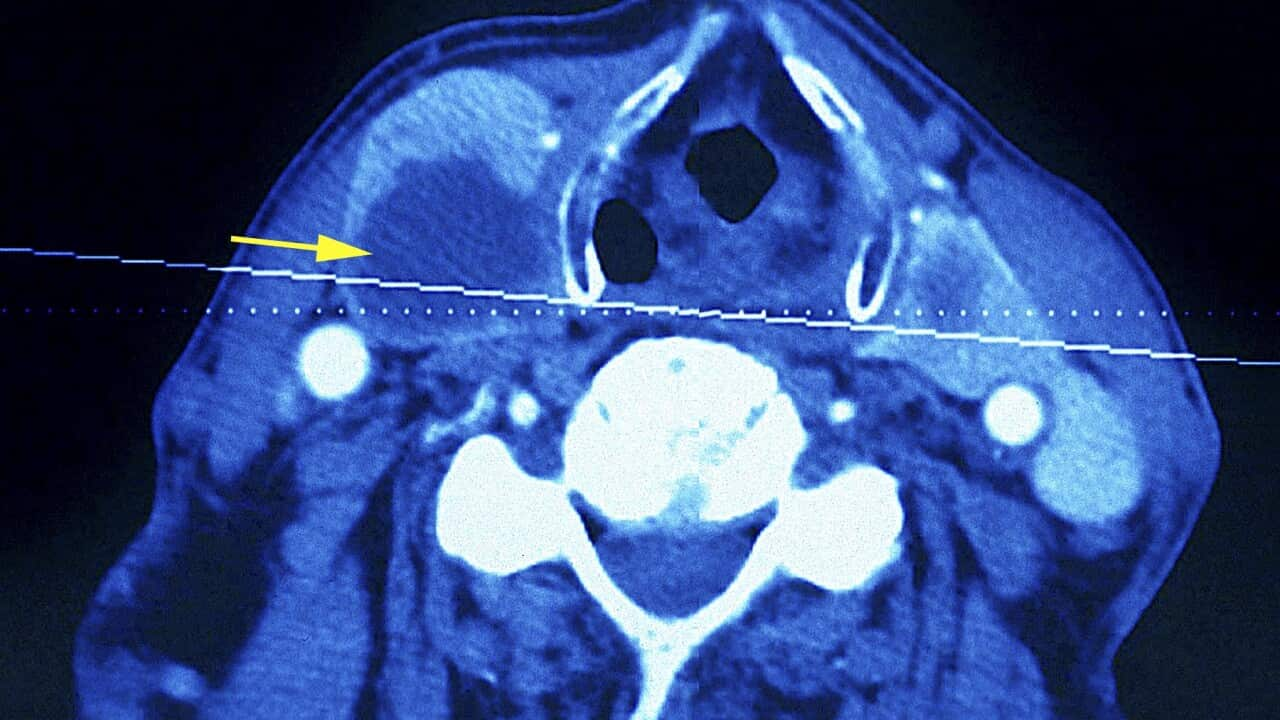

A CT scan of a neck showing a thyroid tumour Source: Getty